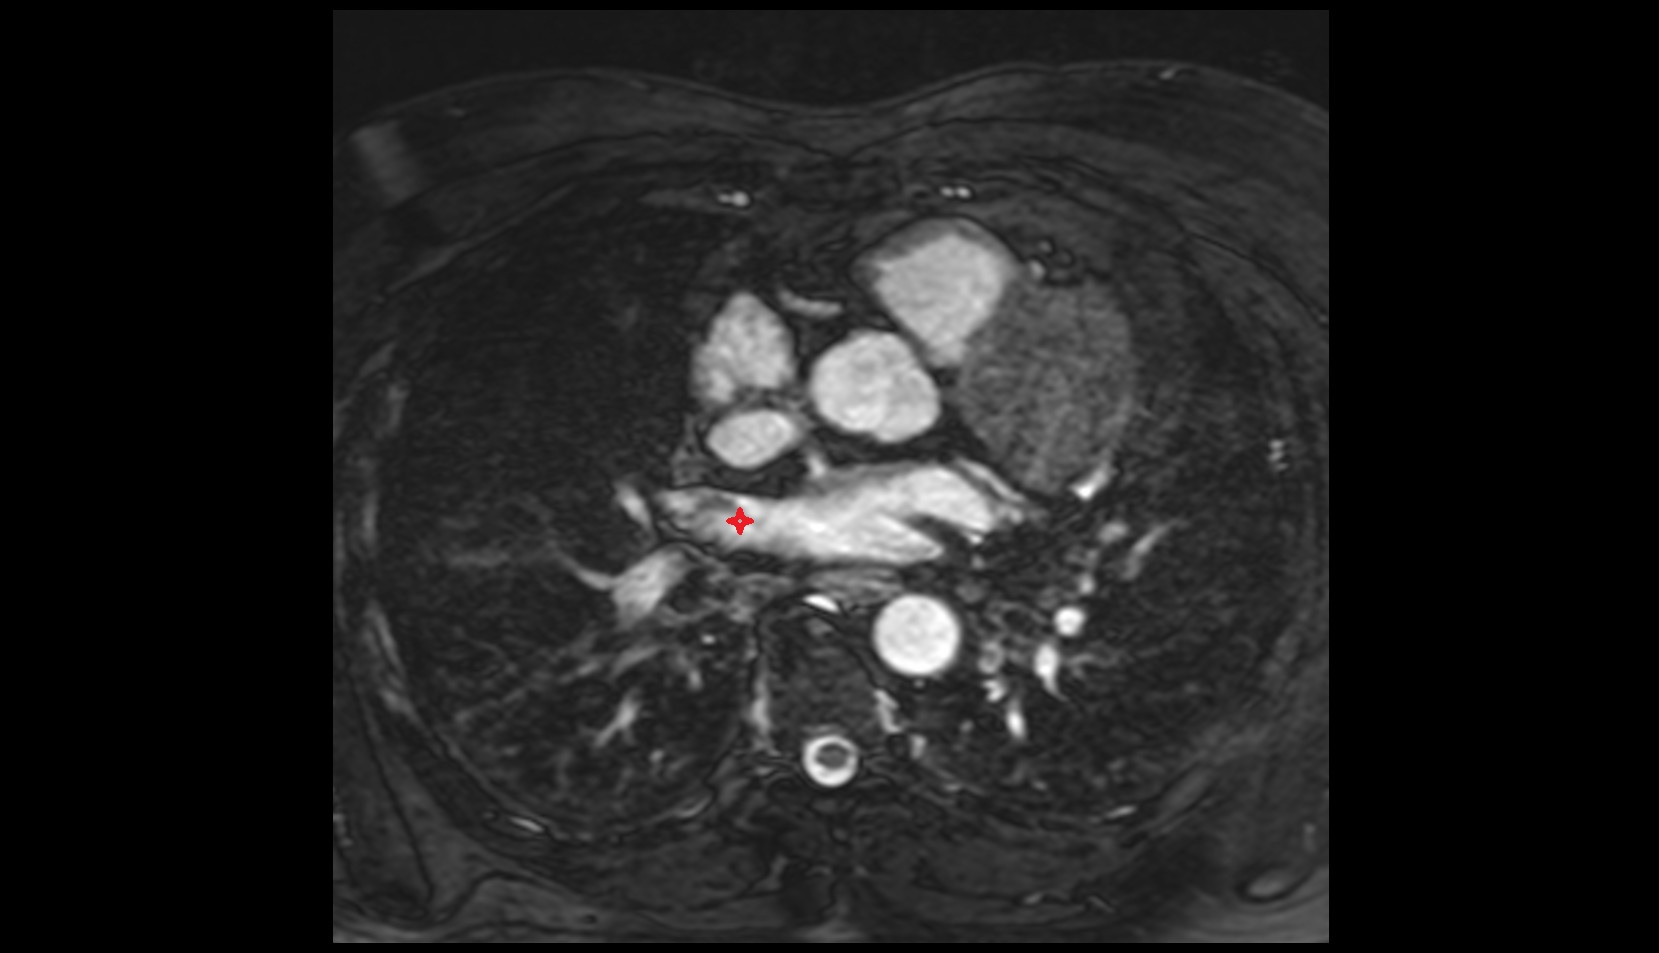

- Left anterior descending artery (LAD)

- Circumflex artery (LCx)

- Left main coronary artery (LMCA)

- Right coronary artery (RCA)